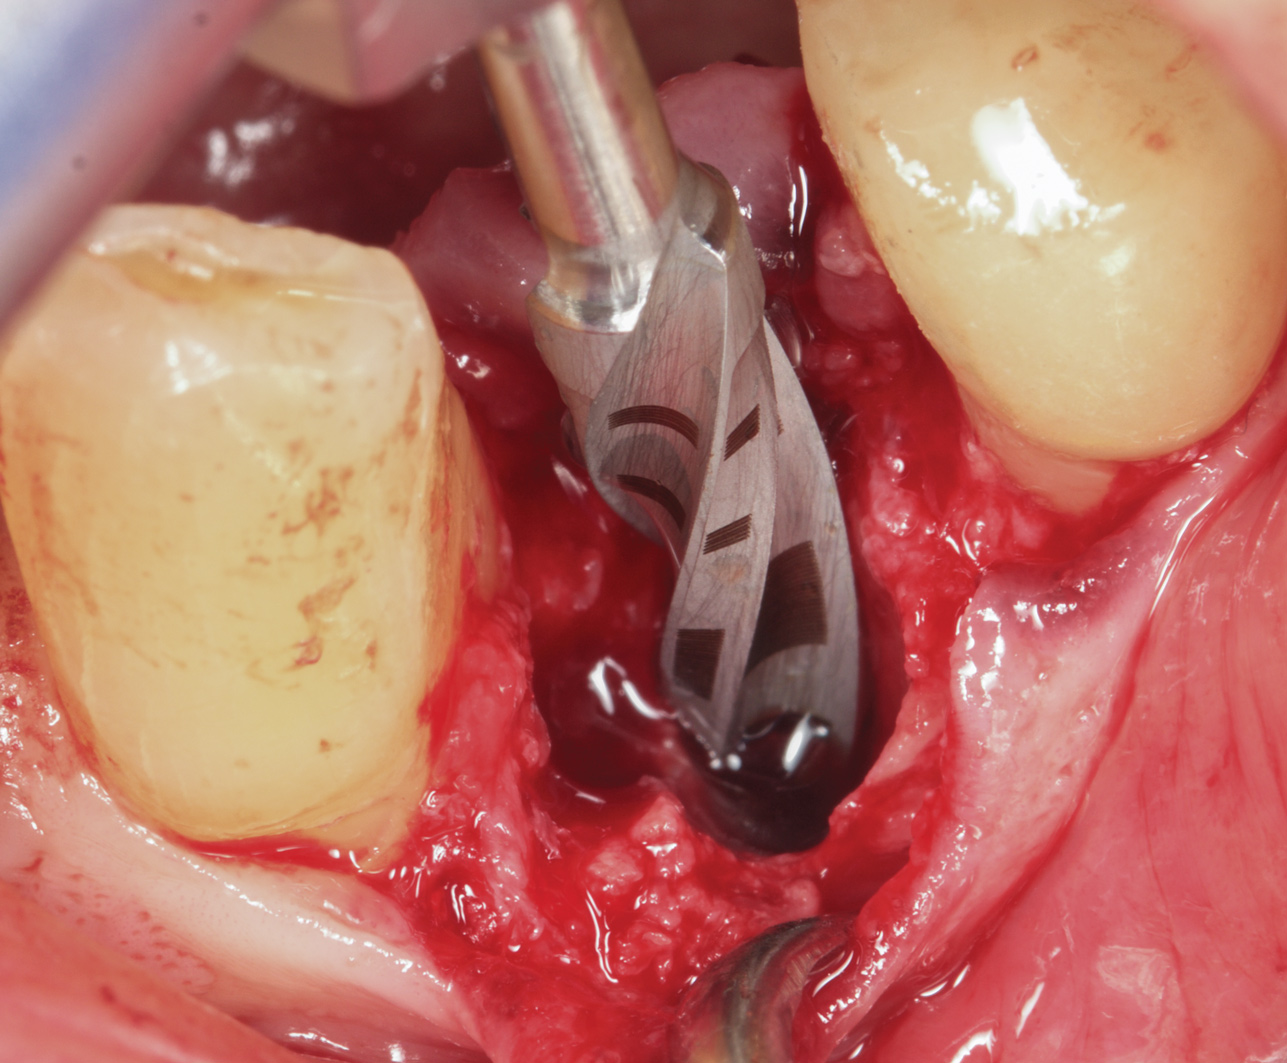

Prior to drilling the osteotomy, a landmark point on the patient scan was verified against direct visualization by placing the drill tip on the chosen anatomical landmark. Surgery proceeded under RADS guidance, in the form of auditory feedback (ie, mode-change and warning beeps) and haptic feedback (ie, resistance to drill motion) as well as visual guidance via a monitor (ie, navigation). To initiate the osteotomy, a 2.3-mm round drill was placed in the robotic guidance arm. As per the implant manufacturer's recommendations, three subsequent drills were used to perform the osteotomy in the prescribed location and angulation (Figure 4 and Figure 5). Implant placement was also achieved with the RADS system (Figure 6 and Figure 7).

Fig 6. Implant placement into the extraction socket under robotic guidance.

Figure 6

Fig 7. Implant placement into the extraction socket under robotic guidance.

Figure 7